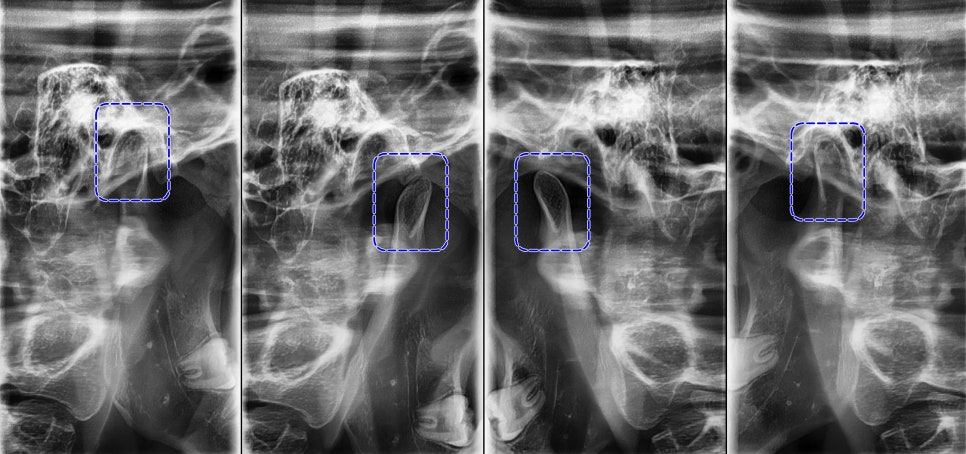

정밀한 검사를 위해

엑스레이를 비롯한 치근단 엑스레이,

턱관절 검사를 통해

치아 교정을 하여도

괜찮은지 확인하는 과정을 걸쳤습니다.